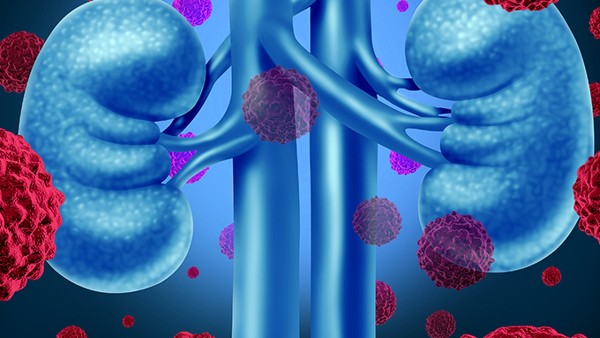

24小时尿蛋白超标怎么办

24小时尿蛋白超标可由疾病(如肾小球肾炎、糖尿病肾病、高血压肾损害等)或生理因素(如剧烈运动、发热等)引起不同人群病因有差异进一步检查包括实验室检查(肾功能、自身抗体、24小时尿蛋白定量)和影像学检查(肾脏超声)针对病因制定治疗方案如肾脏疾病按不同类型用相应药物治疗生理因素导致的去除诱因后定期复查监测需定期复查相关指标关注血压水肿等情况并长期保持健康生活方式。